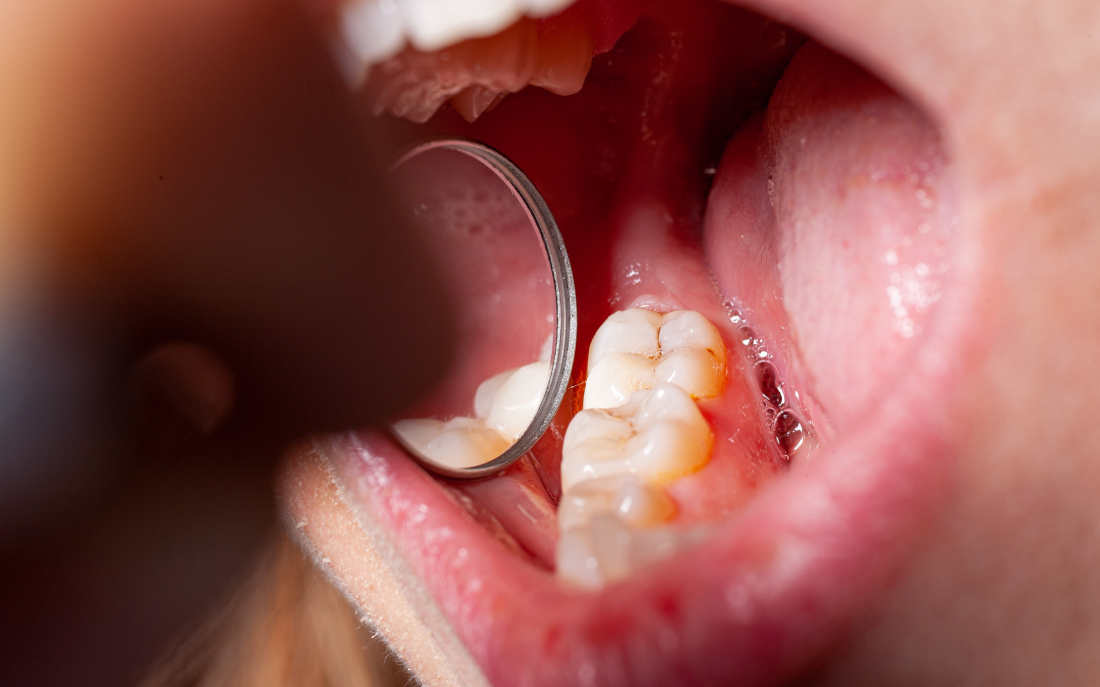

Me quitan los brackets: Todo sobre la retirada y cuidados post-tratamiento La retirada de brackets es un momento clave en el tratamiento de ortodoncia, ya que marca el final de